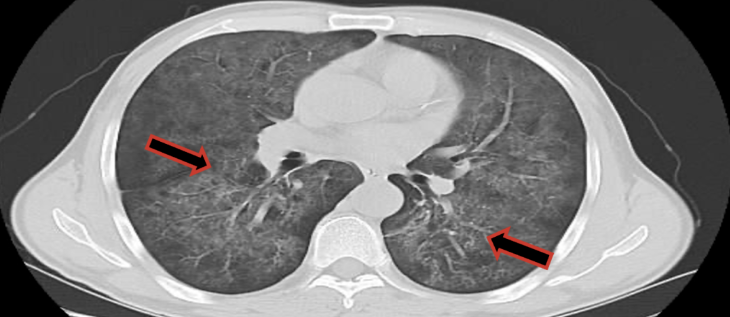

影像学检查:

肺部CT检查报告:检查结果两肺广泛磨玻璃密度灶,建议临床进一步检查除外卡氏肺孢子菌肺炎(图5、图6)。需鉴别诊断:1.大叶性肺炎:胸部CT可见大片的炎症浸润阴影或实变影,其内可见支气管充气征明显,该患者胸部CT可予以排除。2.支气管扩张:表现为慢性咳嗽、大量脓痰、反复咯血、反复肺部感染,查体常有肺部固定性粗湿罗音。胸部片显示肺纹理粗乱或呈卷发状,高分辨CT可见支气管扩张改变。此患者以白痰为主,无咯血,影像学上亦无支气管扩张征象,支气管扩张可除外。